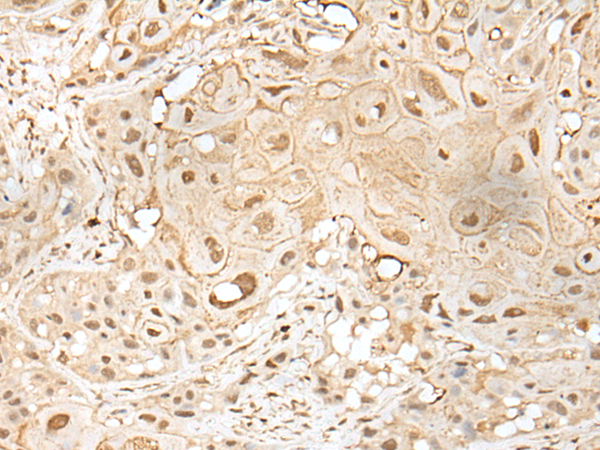

IHC positive control: |

Human esophagus cancer |

IHC Recommend dilution: |

25-100 |